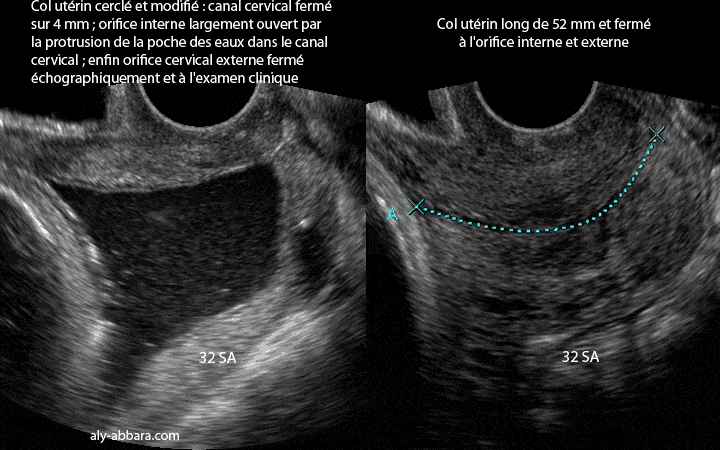

| Image échographique comparant l'aspect d'un col utérin nom modifié (long et fermé) et un col utérin largement modifié : effacement du canal cervical car la longueur restant du canal cervical est de 4 mm seulement, cet effacement du col est provoqué par la protrusion de la poche des eaux dans le canal cervical ; bien sûr la protrusion chez cette patiente était la conséquence de la béance congénitale de l'orifice interne du col utérin déjà mis en évidence lors de la précédente grossesse. On remarque aussi sur cette image le glissement du fil du cerclage du col utérin qui paraît proche de l'orifice externe du col utérin ; il s'agissait d'un cerclage prophylactique réalisé à 18 SA. Enfin, l'orifice externe du col est fermé comme ceci est visible sur cette image et aussi constaté au toucher vaginal. |